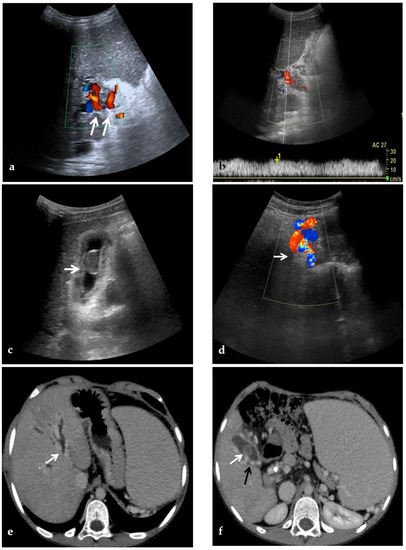

Figure 3.

Color-Doppler Ultrasound and CT images of portal vein thrombosis in a 54-year-old male suffering from liver cirrhosis. (a) Color-Doppler Ultrasound image shows a narrow hepatopetal flow (arrow) despite a large endoluminal thrombus in the extrahepatic portal trunk. (b) Portal phase coronal CT image shows the lack of luminal enhancement and increased portal vein caliber due to a large endoluminal thrombus in the extrahepatic trunk (arrow). (c) Portal phase axial CT image shows the extension of the portal vein thrombosis up to the splenomesenteric confluence (white arrow); liver cirrhosis is visible on the the liver surface that presents lobulated margins (black arrows).

A CT scan in the pre-contrast phase can show hyperattenuating material in the portal vein. After contrast injection, lack of luminal enhancement increased portal vein caliber, increased arterial hepatic enhancement, and decreased portal hepatic enhancement are typical findings of PVT [28] (Figure 3 and Figure 4). Transient hepatic attenuation differences related to altered hepatic perfusion can also be demonstrated on CT with geographic areas of increased attenuation at the periphery of the liver on arterial phase imaging. These transient attenuation differences are related to decreased portal venous perfusion and compensatory increased arterial perfusion from the periphery of the liver [46,49].